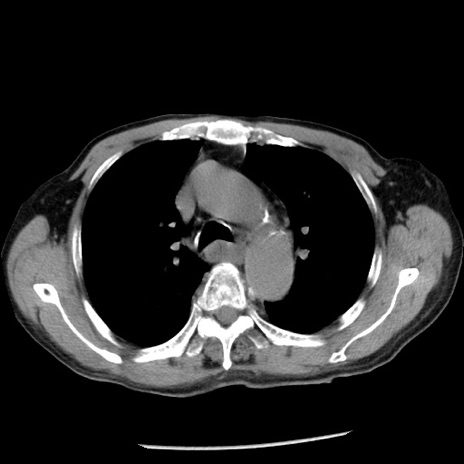

冠状断像

【症例】80歳代男性

【主訴】嘔吐

【現病歴】昨晩2回嘔吐あり、今朝になっても嘔吐あり。来院。

【既往歴】胃潰瘍

【身体所見】意識清明、BT 37.6℃、BP 166/95mmHg、HR 100bpm、SpO2 97%、腹部:平坦・軟、腸蠕動音聴取良好、圧痛なし。

【データ】WBC 21900、CRP 1.46